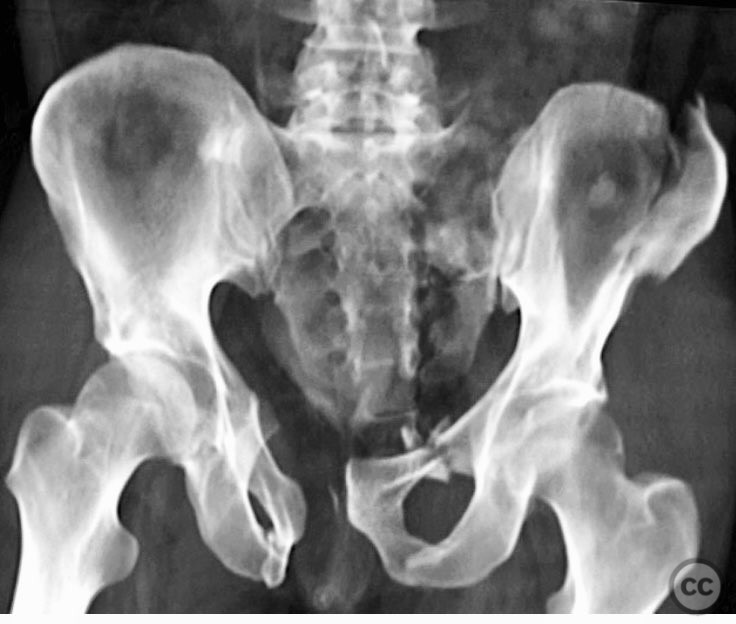

Clinical and radiological findings:  A 42-year-old male sustained a high-energy motor vehicle accident resulting in an unstable pelvic ring injury (AO/OTA 61-C1.3) with hemodynamic instability and associated intraperitoneal bladder rupture. Initial computed tomography demonstrated a complex anterior pelvic ring disruption and a posterior sacral fracture with contrast extravasation and blood within the fracture site. The patient was hemodynamically unstable on presentation.

Planning remarks:  The preoperative plan included multidisciplinary management with urology for bladder repair, followed by open reduction and internal fixation of the anterior pelvic ring via an anterior approach. Subsequent posterior pelvic stabilization was planned after initial resuscitation and anterior fixation, utilizing a posterior approach for direct sacral reduction and percutaneous iliosacral screw fixation.

The case was notable for initial successful multidisciplinary management of both hemodynamic instability and intraperitoneal bladder injury, allowing for staged surgical intervention. Despite accurate anterior pelvic reduction and fixation, postoperative imaging revealed worsening posterior sacral displacement, necessitating subsequent posterior open reduction. The use of a tenaculum clamp facilitated direct anatomical reduction of the sacral fracture prior to iliosacral screw fixation. The presence of an embolic coil from prior angioembolization did not impede surgical access or hardware placement. This case demonstrates that initial anterior pelvic ORIF does not complicate or preclude subsequent routine posterior pelvic ORIF in complex unstable ring injuries.